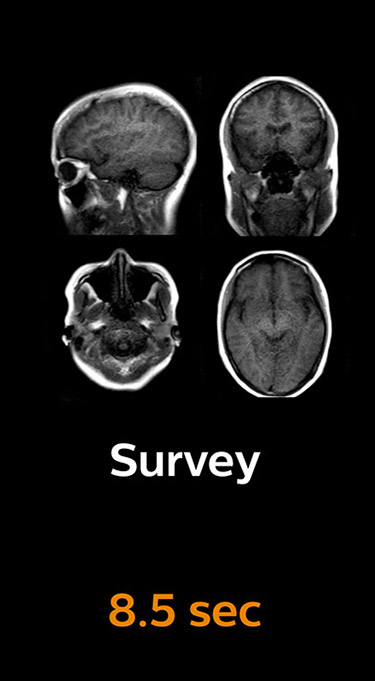

Scanning time reduction in brain MRI with Compressed SENSE

Fast MRI of brain

With Compressed SENSE, the scan time for the routine brain examination at KNC was reduced from 15:48 to 10:19 minutes, which corresponds to 35% reduction.

Ingenia 3.0T CX

Scan time 15:48 min.

Brain with Compressed SENSE

Ingenia 3.0T CX

Scan time 10:19 min.